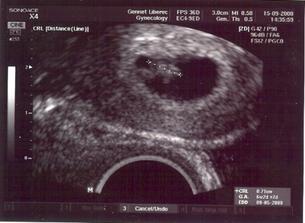

12.9.2008 kontrolní ultrazvuk - už v pondělí jsem začala krvácet a bohužel jsme o jednoho mimíska přišli☹

ale druhý mimísek je v naprostém pořádku a bije mu srdíčko🙂) .............................................

26.9.08 utz ko - mimísek už má 22mm a je v pořádku.............................................